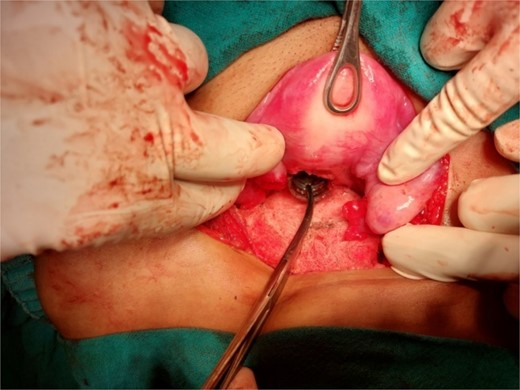

A 26-year-old nulliparous lady from a rural area was referred to emergency from a primary health care centre with a failed attempt to remove an impacted uterine foreign body. On per speculum examination, an impacted hard pipe-like structure was protruding from the cervix. The patient gave a history of foreign body insertion 9 years back, however, failed to provide a detailed account of the mode of insertion or history of sexual assault. She went to seek medical care only after developing profuse foul-smelling discharge and chronic pelvic pain. Removal was attempted under local anaesthesia but failed. Transvaginal scan showed a bulky uterus with an apparently normal endometrial thickness and echotexture; however, the cervical canal was distended with an echogenic area and areas of calcification (Figs 1 and 2). She was taken up for removal of the foreign body under general anaesthesia. As a hard pipe-like structure was already protruding, removal was tried by grasping it with a Kocher’s forceps. After multiple attempts part of the foreign body was removed. Hysteroscopy showed that the lower endocervical canal was clear and a ring-like structure occupied the upper endocervical canal. Removal under direct vision using a hysteroscopic grasper was attempted but failed due to the impaction and size of the object and the hysteroscope could not be negotiated beyond the object. A laparotomy was performed and after an assessment of anatomy and tactile sensation to assess accessibility, incision on the posterior surface of the uterus was given (Figs 3 and 4) and the object was removed (Fig. 5). The incision was closed in two layers. Intercede was placed at the repair site. An extended course of antibiotics was given for 7 days. Post-operative recovery was uneventful. Contraception for at least 1 year, the need for proper antenatal care, the risk of rupture, and mandatory caesarean delivery were counselled to the couple.

Extraction of the foreign body through a posterior hysterotomy incision.